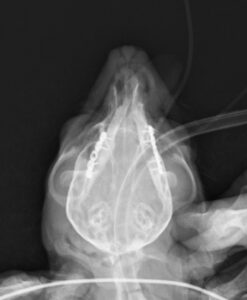

重度の歯周病で両側の下顎の病的骨折をしているワンちゃんが来院されました。悪い歯の抜歯と下顎のプレート固定(TITAN LOCK1.2mm使用)で対応しました。退院後しっかりご飯が食べられるようになりました。よかったね。